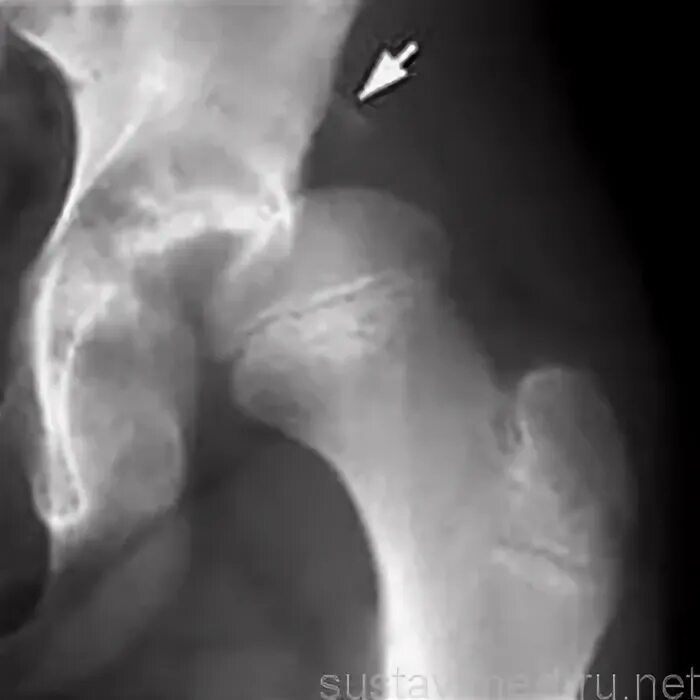

Вывих тазобедренного у взрослых